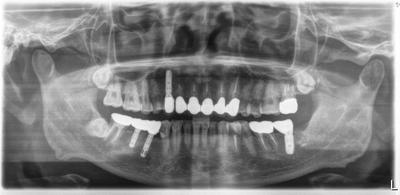

インプラントを含む包括診療。

右下インプラントは他院において行われたものであるが、補綴物破損、インプラント周囲炎に罹患していたため、インプラント周囲炎への対応後、補綴物を再製作している。このインプラントは今は販売されていないIMZ(ドイツ)のものだが、パーツの供給は継続されていたため、補綴物の再製作は可能であった。

当院で行ったインプラント治療はアストラテックのものを使用している。